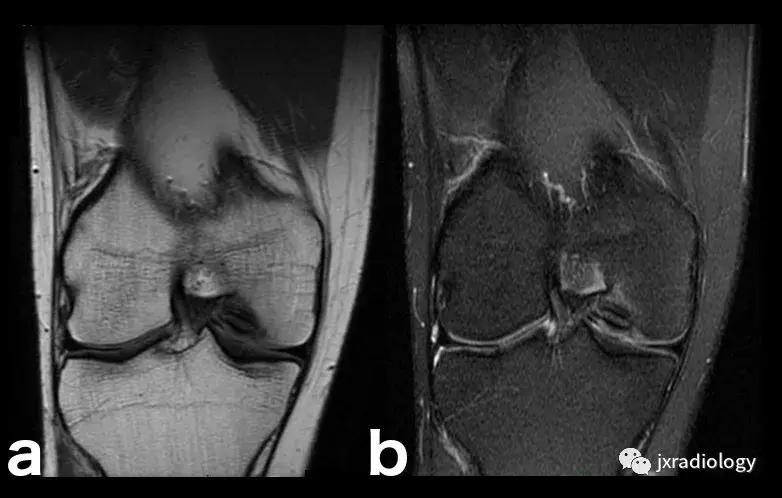

图19:剥脱性骨软骨炎(OCD)。 与图18相同的患者。X线片显示右侧股骨内侧髁见骨软骨碎片。